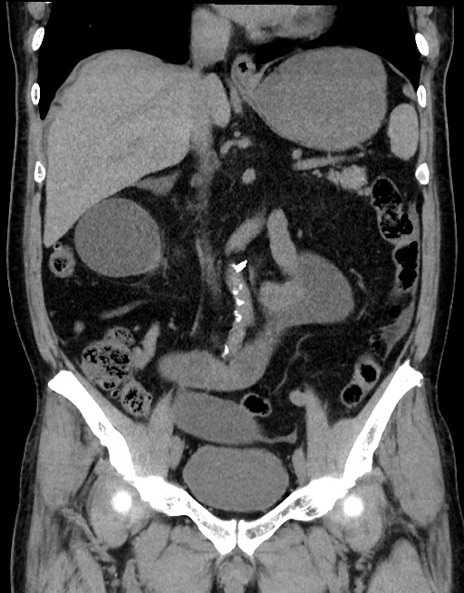

症例15(冠状断像)

【症例】70歳代男性

【主訴】腹痛

【現病歴】今朝から腹痛あり。全体的に痛い。特に左上の方。排ガスが今日はない。冷や汗が出る。

【既往歴】直腸癌術後

【身体所見】左側腹部〜上腹部に圧痛あり。腹膜刺激症状明らかなではない。軽度反跳痛。左下腹部に術後瘢痕あり。

【データ】WBC 7700、CRP 0.02